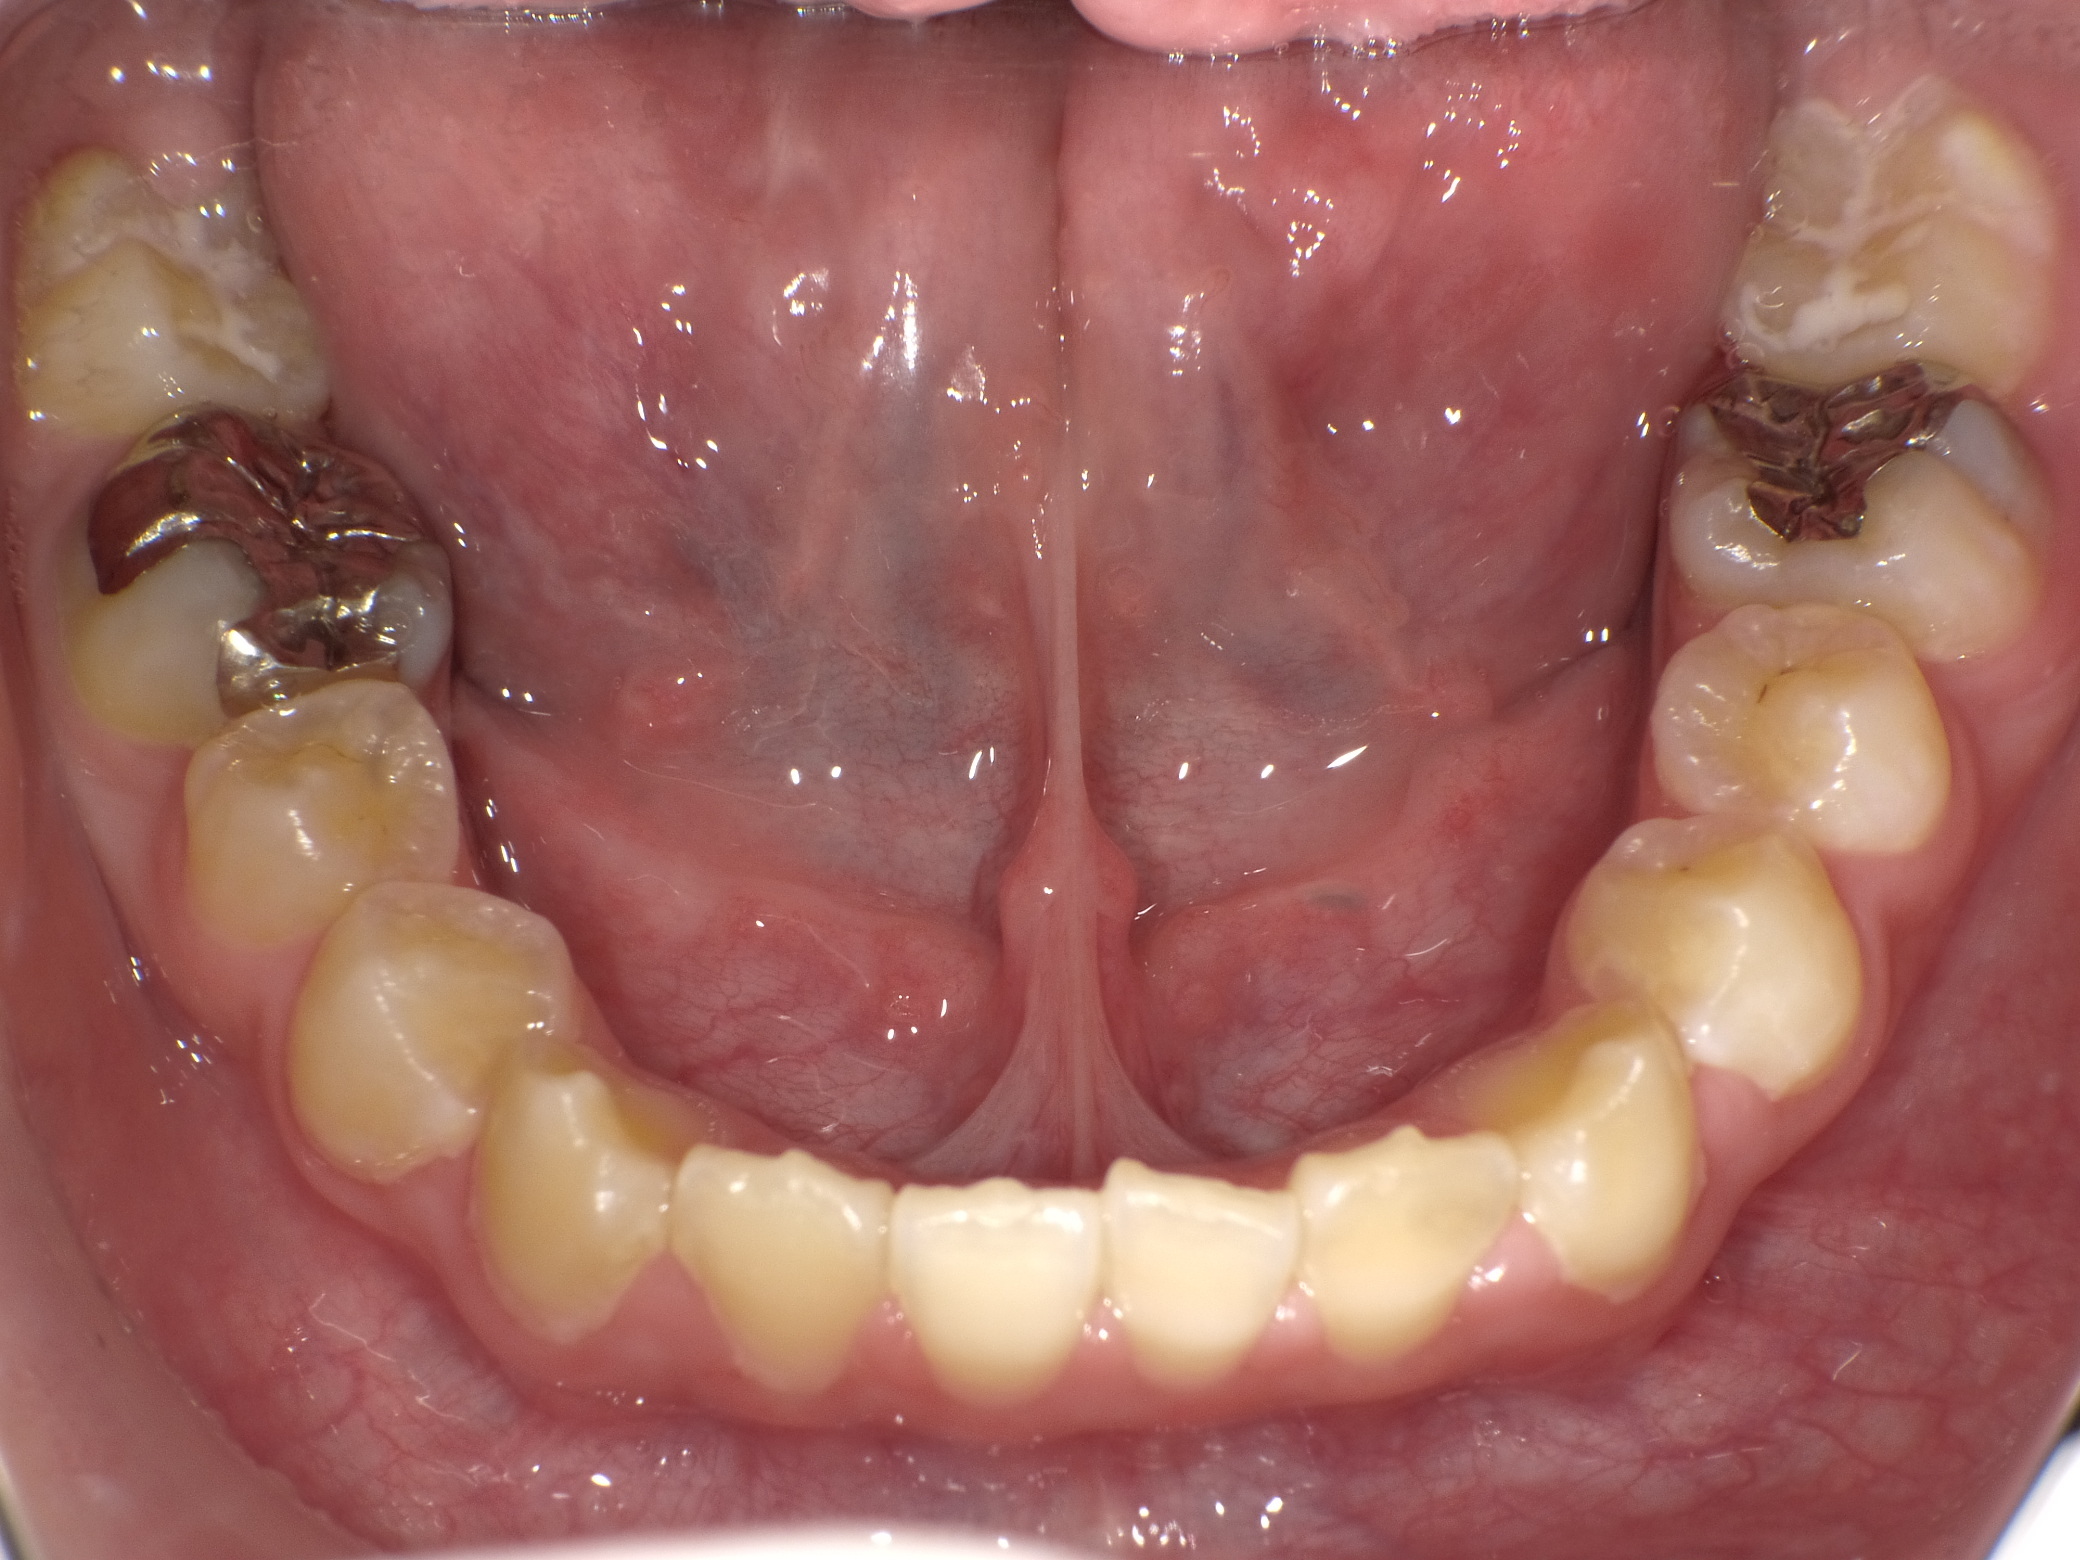

実際の症例

治療前です 下の奥歯が著しく崩壊しています

本来なら神経を取る治療を行うと思いますが、ドックスセメントにて神経の保護をはかりました